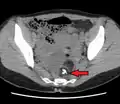

- A complex cyst due to a dermoid as seen on CT. Arrow points to bone or teeth.